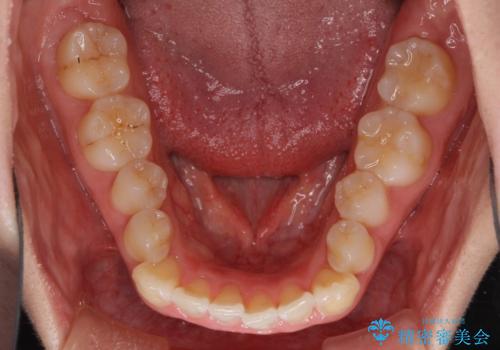

- 口元の突出感と口の閉じにくさ、前歯のデコボコを気にして来院された患者様です。

上下左右第一小臼歯4本を抜歯し、ワイヤー装置にて口元を引っ込めるよう矯正治療を行うこととしました。